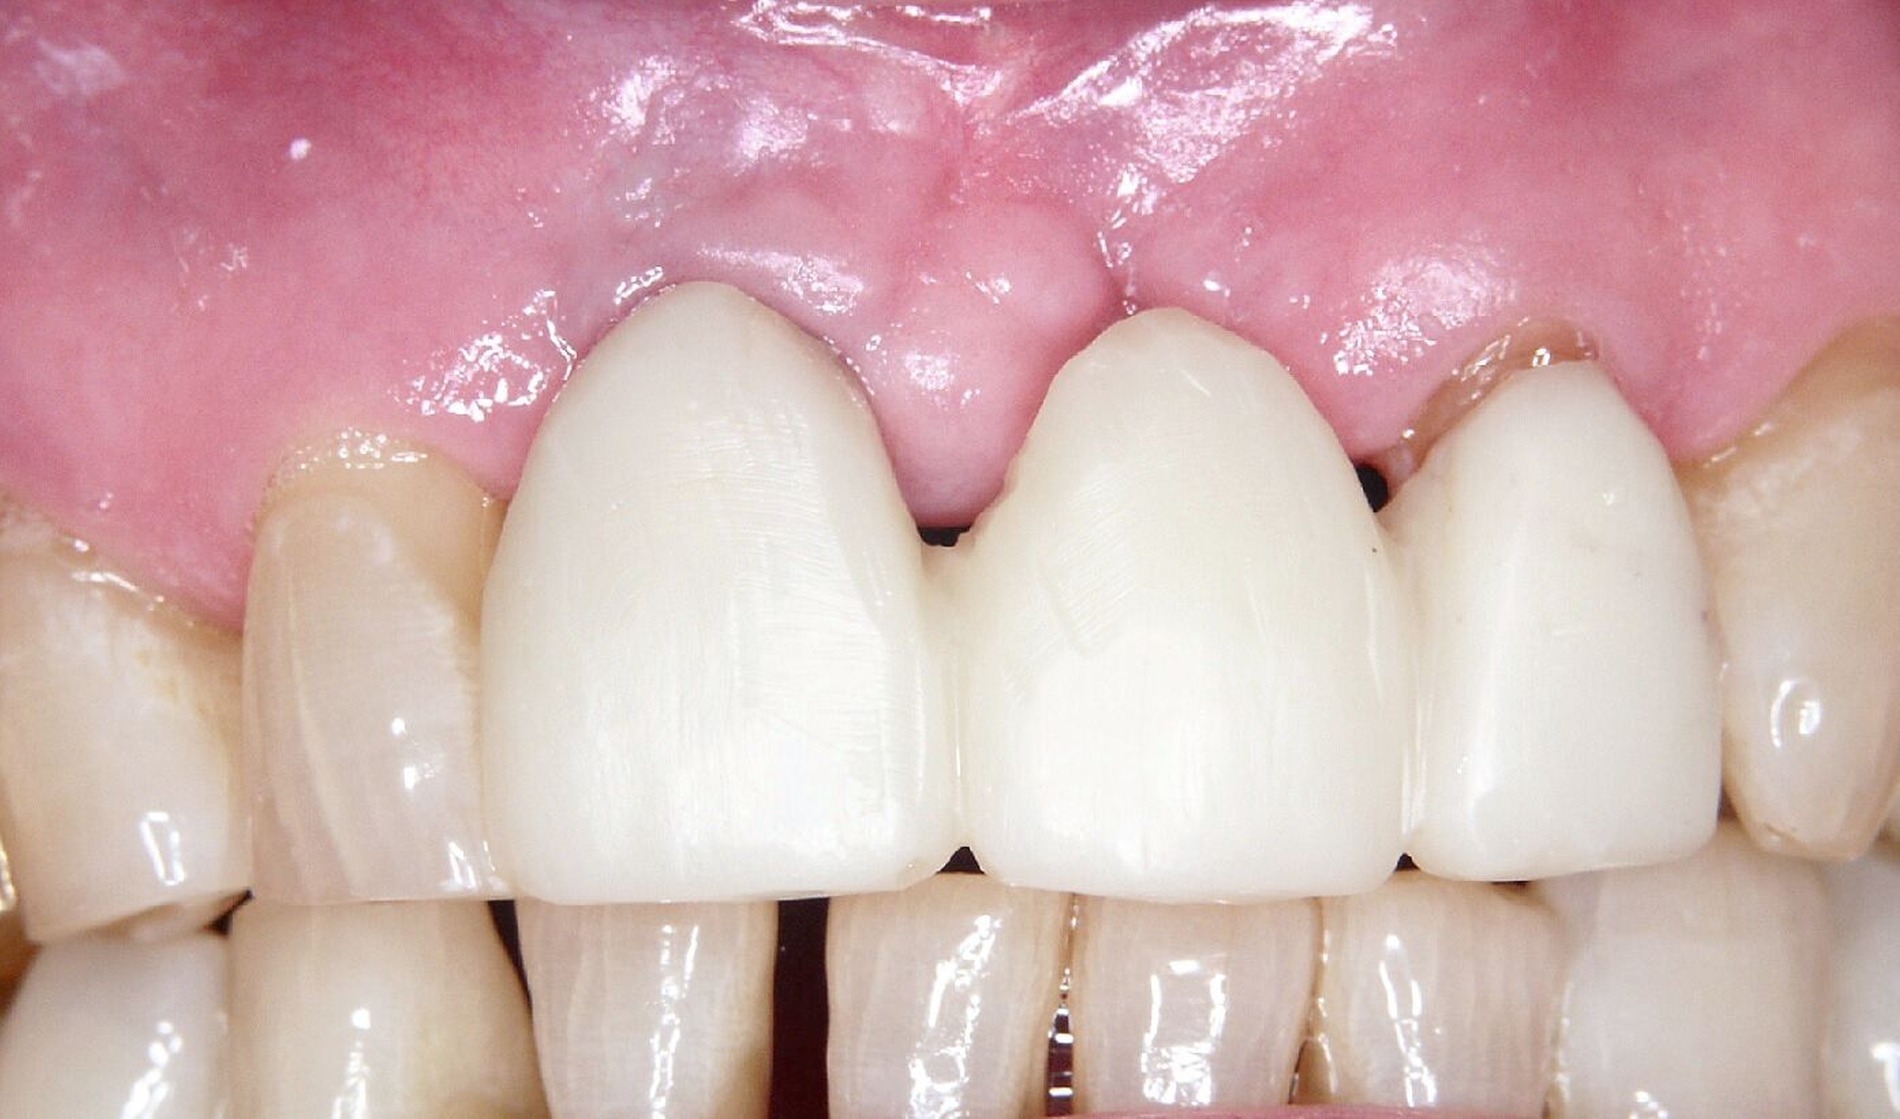

Ursprünglich waren bei dieser Patientin nach einem Frontzahntrauma vier Implantat-gestützte Kronen geplant. Nach dem frühen Verlust des Implantats in regio 21 während der Einheilzeit wurde dann eine auf drei Implantaten abgestützte Brücke eingegliedert. Das bestehende vertikale und horizontale Weichgewebsdefizit wurde bei der verschraubten Implantatbrücke durch aufgebrannte rosafarbene Keramik kaschiert (Abb. 3a). Funktionell war die Brückenversorgung über viele Jahre erfolgreich und zeigte keinerlei Lockerungsgrad. Trotz guter Mundhygiene war in Kontrollsitzungen ein kontinuierlicher Knochenabbau an allen Implantaten festzustellen (Abb. 3b). Zur Vermeidung eines weiteren Knochenverlusts fiel circa 15 Jahre nach der Erstversorgung die Entscheidung zur Explantation. Zu diesem Zeitpunkt war die Patientin 55 Jahre alt.

Da sechs Monate nach der Explantation keine nennenswerte knöcherne Regeneration festzustellen war, wurde eine zweizeitige Implantation nach Knochenaugmentation mithilfe dünner Knochenscheiben aus dem Kieferwinkel geplant. Die Entnahme erfolgte mit oszillierenden Instrumenten (Piezosurgery). Der Knochenblock wurde in dünne Scheiben geschnitten und mit Osteosyntheseschrauben am Alveolarfortsatz fixiert (Abb. 3e). Darüber wurden die Weichgewebe dicht vernäht. Weitere fünf Monate später erfolgte die Schraubenentfernung und die Implantation von zwei Bone-Level-Implantaten in regio 12 und 22 mit geschlossener Einheilung (Abb. 3f und 3g). Bei der Implantatfreilegung weitere sechs Monate später wurden die Weichgewebsdefizite im Brückengliedbereich durch ein kombiniertes Bindegewebs-/Schleimhauttransplantat aufgefüllt und gleichzeitig die keratinisierte periimplantäre Gingiva und Alveloarmukosa verbreitert (Abb. 3h und 3i). Die prothetische Versorgung erfolgte erst weitere drei Monate später, nach dem Konsolidieren der Weichgewebe. Die umfangreichen Augmentationsmaßnahmen konnten das transversale Weichgewebsdefizit vollständig kompensieren, während das verbleibende vertikale Defizit zu zervikal etwas längeren Kronen und Brückengliedern führte. Aufgrund der guten Abdeckung durch die Oberlippe kann das ästhetische Ergebnis als zufriedenstellend bewertet werden (Abb. 3j bis 3l).